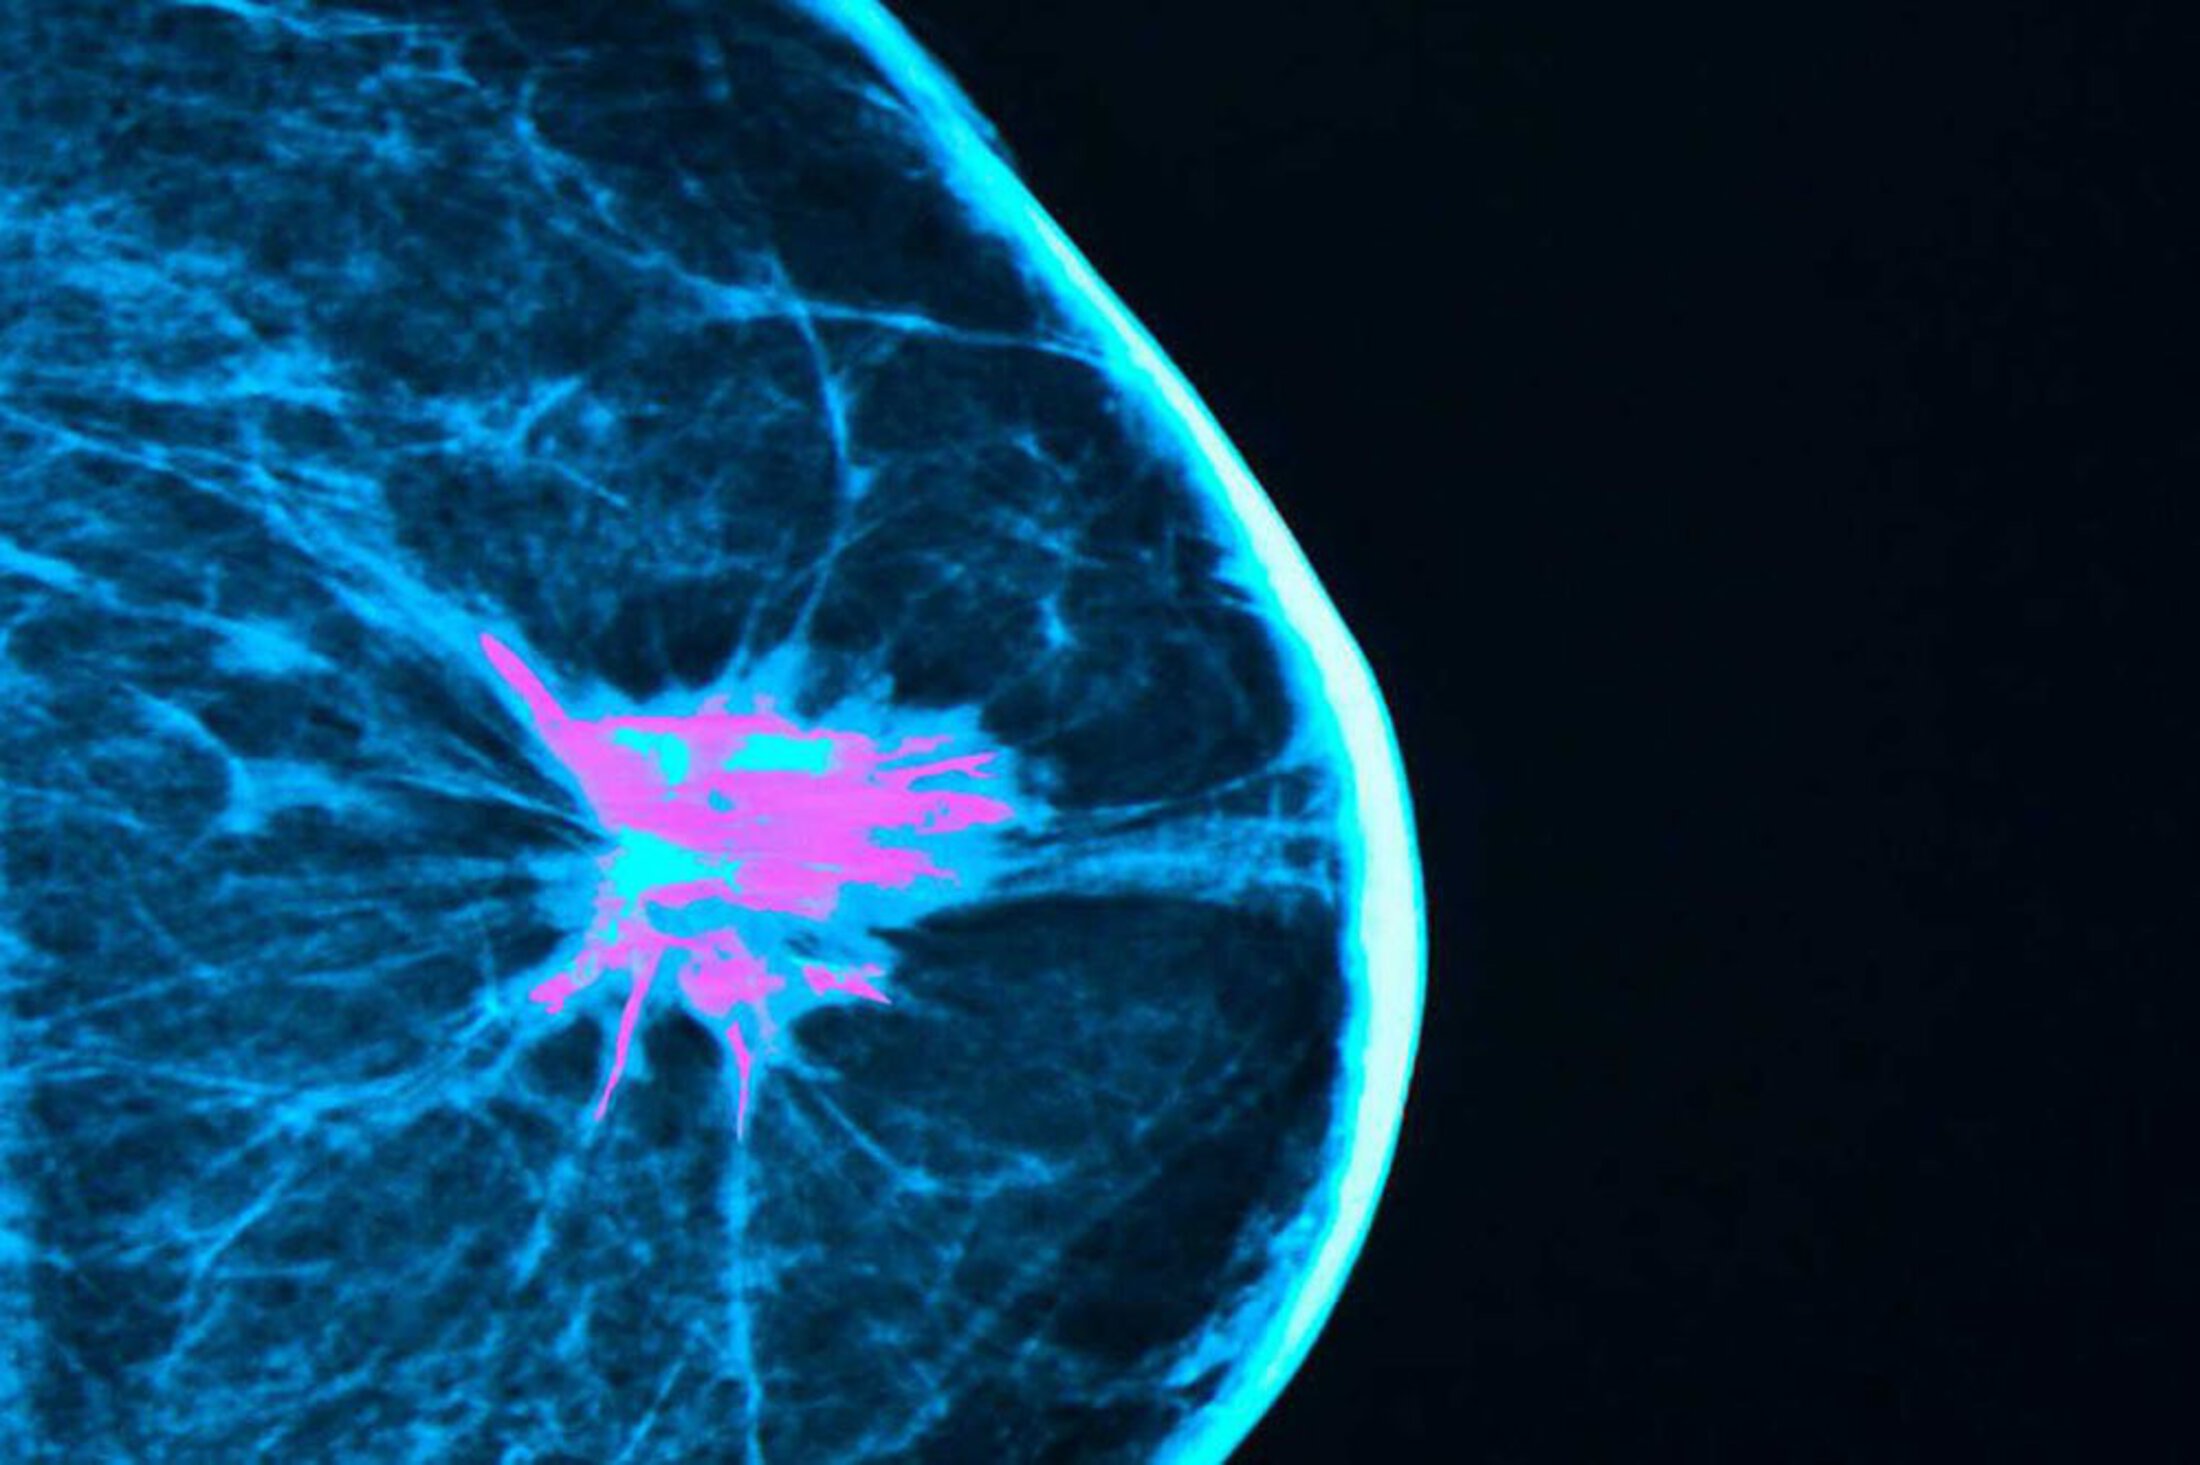

A new breast cancer database could help lay the groundwork for personalized treatments based on unique gene changes in each patient's cancer. iStock